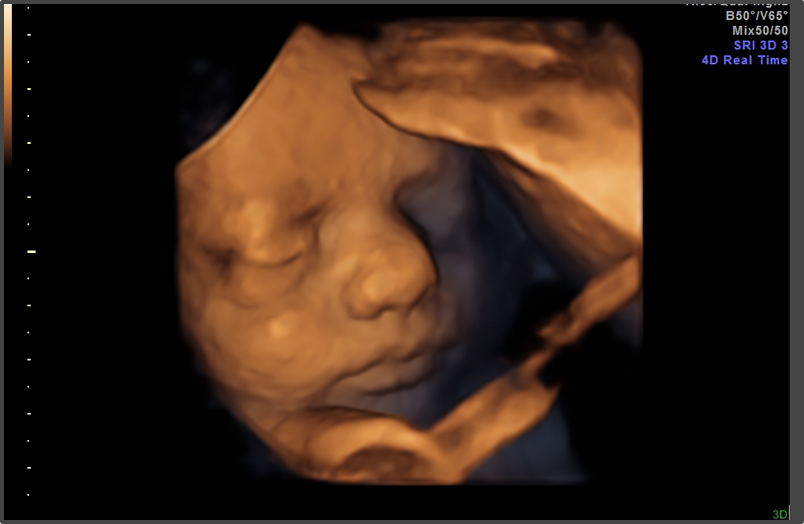

Ултразвук

(34 гестационна седмица)

През 34 седмица от бременността е много вероятно да посетите вашия Акушер- гинеколог и да направите ултразвуков преглед. Може да се направи и Биофизичен профил (BPP) по преценка на лекаря, който представлява комбинация от ултразвук и специален безстресов тест, който измерва сърдечната честота на бебето за определен период от време. Заедно тези два теста помагат на лекаря да потвърди, че бебето реагира добре на стрес и процъфтява.

34 гестационна седмица – снимка: thebirthcompany.co.uk